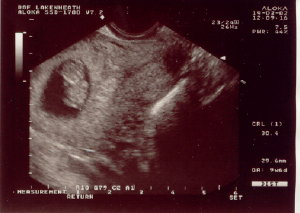

Here are some Ultrasound Pictures we took when the baby was only 8 weeks old...